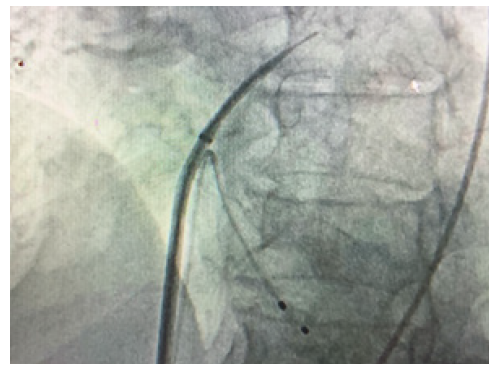

After repeated attempts it was decided to try an alternative approach. The right femoral vein was accessed and an 8F sheath inserted. Transeptal puncture was performed with a Brockenbrough needle and long Terumo wire passed through the left atrium to the left ventricle. The wire could then easily pass retrogradely through the aortic valve down to the descending aorta. The wire was then snared out of femoral artery. A multipurpose catheter was then passed over the wire and antegradely into the left ventricle and the guide wire exchanged. Finally, he nailed the wire to the right sheet of the TAVI. By pulling like this, the wire of the TAVI could cross the calcified valve. The cardiologist after passing the wire through aortic calcified valve put a balloon for the dilatation of the very stenotic valve. This venous-arterial wire loop is used to pass TAVI catheter through aortic valve. After the dilatation of the stenotic aortic valve with the balloon, the procedure continues as standard transfemoral approach. Medtronic Evolut valve was implanted successfully (Figure 1)(Figure 2)(Figure 3).

Figure 2: The wire goes from vena cava, right atrium,left atrium, left ventricle, aorta then femoral artery.